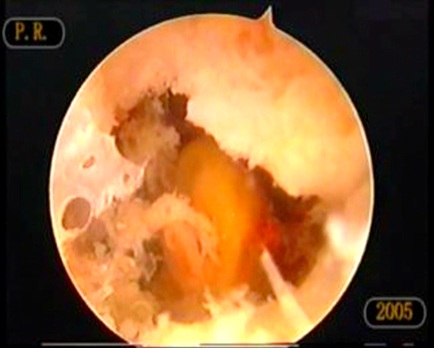

Figure 3: Arthroscopic finding showing reddish membranes.

MRI and CT showed fluid in the bone (Figure. 2). Arthroscopic curettage without bone grafting was performed. A 6-mm skin incision was used to aspirate the bloody fluid and remove the cyst membrane (Figure 3). Pathologic examination demonstrated the cyst to be an ABC (Figure. 4). Curettage was performed using the arthroscope. Range of motion exercices were begun on the first postoperative day. The outcome was good and there was no evidence of recurrence at the 20-month follow-up (Figure. 5).